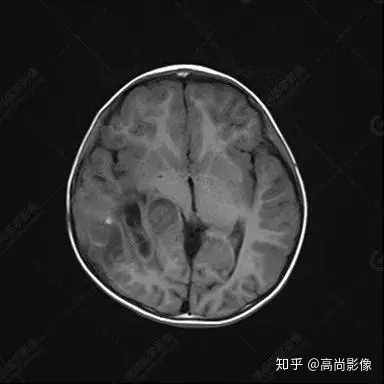

右側(cè)顳葉腫瘤切除術(shù)后(具體不詳):右側(cè)顳部骨質(zhì)不連續(xù)呈術(shù)后改變,右側(cè)顳葉術(shù)區(qū)見片狀長T1長T2信號(hào)影,F(xiàn)LAIR呈低信號(hào);術(shù)區(qū)后方右側(cè)顳枕葉見一巨大占位性病變影,邊界欠清,大小約6.2×5.8×4.3cm(前后×左右×上下),信號(hào)不均勻,T1WI呈等稍低信號(hào)間雜少許高信號(hào),T2WI呈高稍低混雜信號(hào),DWI示部分病灶彌散受限,相應(yīng)ADC圖減低,磁敏感序列見部分呈極低信號(hào),增強(qiáng)掃描可見明顯不均勻強(qiáng)化,鄰近硬腦膜及小腦幕增厚并明顯強(qiáng)化;另延髓右前方及右側(cè)橋小腦角區(qū)見一不規(guī)則形異常信號(hào)影,大小約3.2×1.3×3.7cm(左右×前后×上下),呈長T1稍長T2信號(hào),F(xiàn)LAIR呈等信號(hào),DWI未見受限,增強(qiáng)后明顯均勻強(qiáng)化,鄰近腦膜明顯強(qiáng)化。鄰近腦實(shí)質(zhì)及右側(cè)顳角明顯受壓;左側(cè)大腦半球未見局灶性信號(hào)異常,中線結(jié)構(gòu)稍左移。

右側(cè)顳葉腫瘤切除術(shù)后:現(xiàn)術(shù)區(qū)后方右側(cè)顳枕葉及延髓右前方占位,右側(cè)顳枕部硬腦膜及小腦幕明顯強(qiáng)化,結(jié)合既往影像資料,考慮為胚胎源性惡性腫瘤,如非典型畸胎樣/橫紋肌樣瘤(AT/RT)或原始神經(jīng)外胚層腫瘤(PNET)。